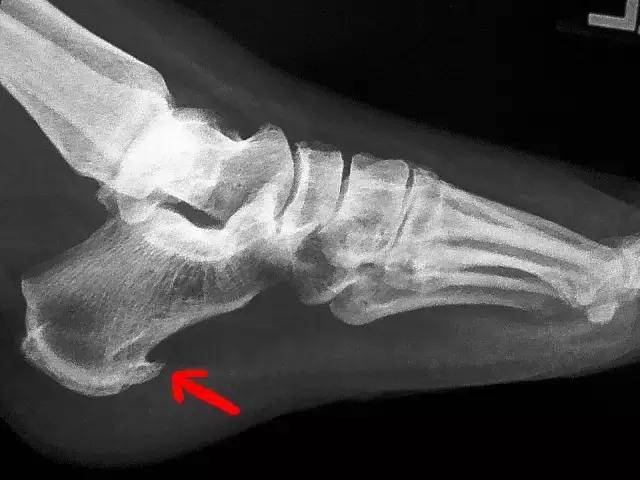

尤其是弓和弦的连接处——脚后跟,最容易出问题。这个地方反复受到刺激和损伤,导致了在应力(弦)的方向骨刺的形成,所以我们仔细观察X光片会发现,骨刺方向是水平而不是垂直向下的。